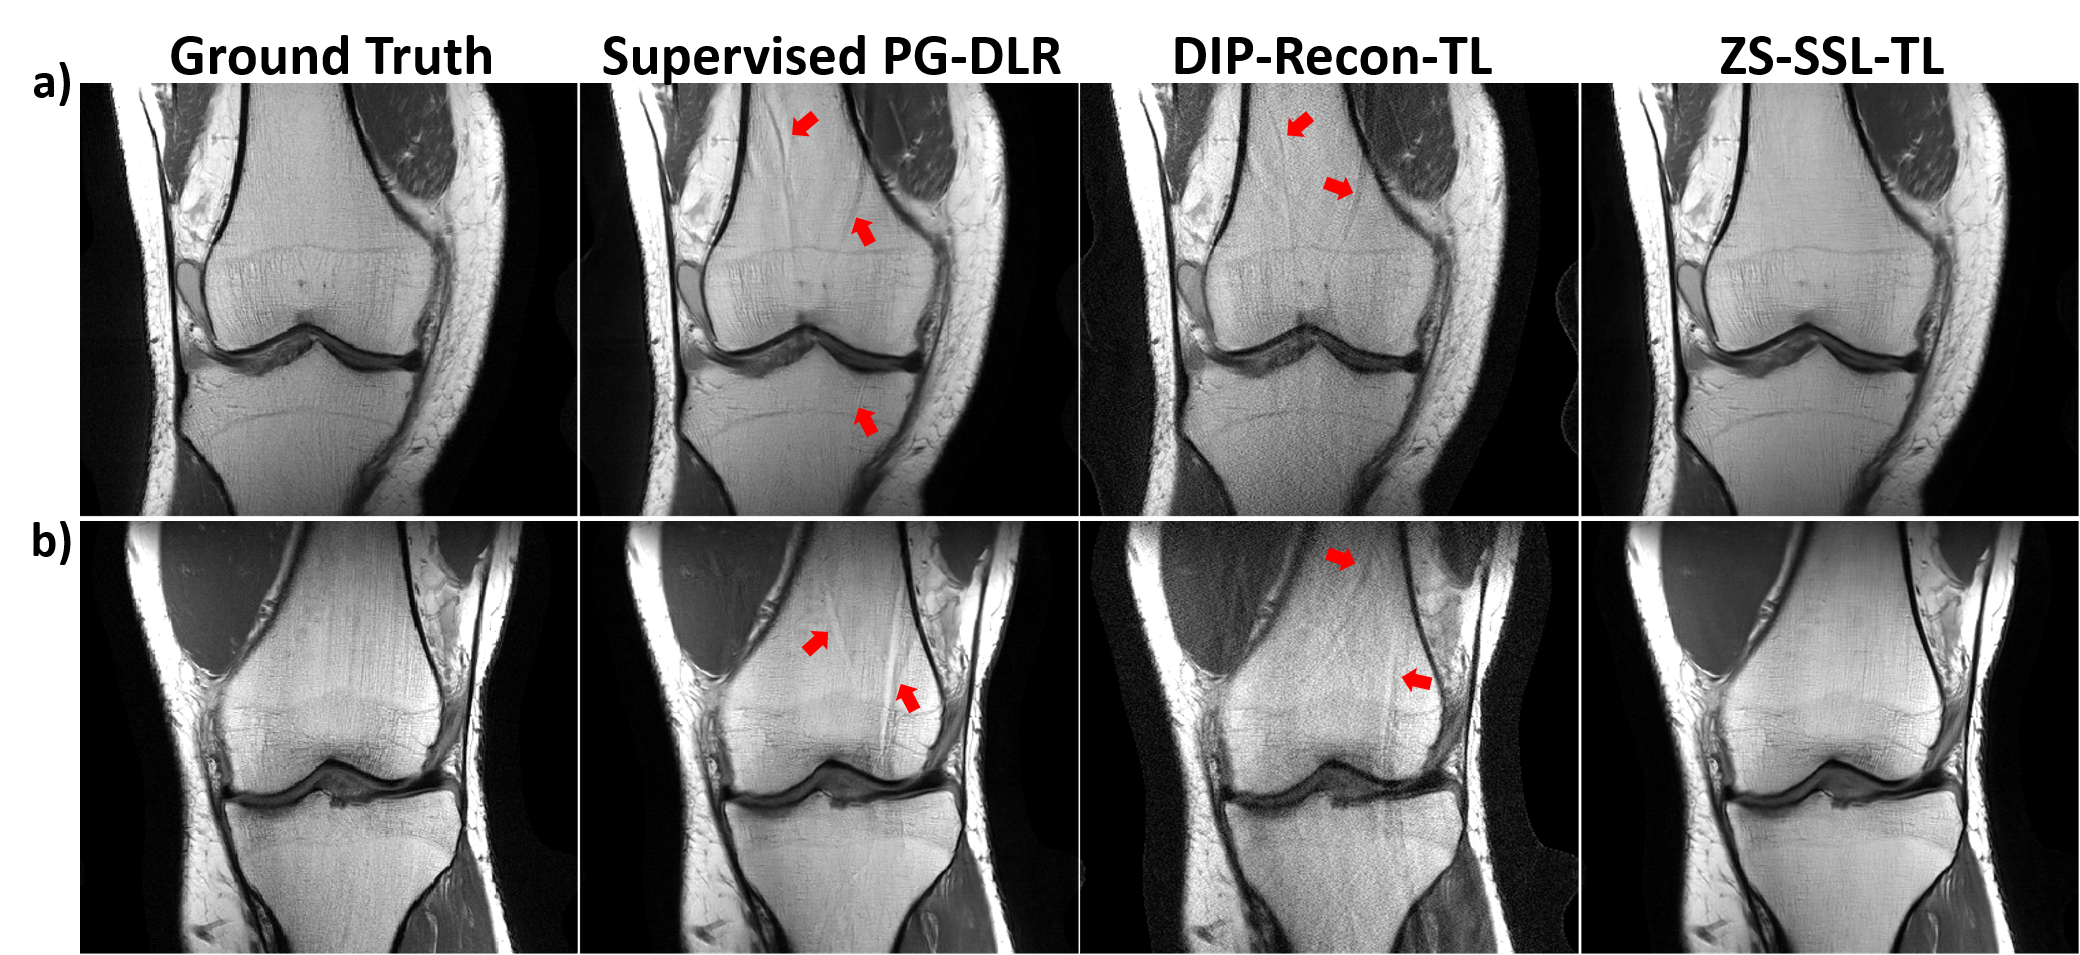

Cross-Domain Transfer: In the last set of experiments, we investigated the cross-domain generalizability of database-trained PG-DLR compared to subject-specific trained PG-DLR. For cross-domain transfer, training and test datasets are of the different data characteristics and generally differ in terms of contrast, SNR, and anatomy (Figure 11 in the Appendix). Figure 6 shows results for the case when the testing contrast/SNR and anatomy differs from training contrast/SNR and anatomy, even though the same R = 4 uniform undersampling is used for both training and testing. In Figure 6a, supervised PG-DLR was trained on Cor-PDFS (low-SNR), but tested on Cor-PD (high-SNR and different contrast). In Figure 6b, supervised PG-DLR was trained on Ax-FLAIR (brain MRI) and tested on Cor-PD (knee MRI). In both cases, supervised PG-DLR fails to generalize and has residual artifacts (red arrows). Similarly, DIP-Recon-TL suffers from artifacts and noise. ZS-SSL-TL achieves an artifact-free improved reconstruction. For both cross-domain transfer experiments, similar results were observed for brain MRI (Figure 12 in the Appendix). Average PSNR and SSIM values match these observations (Table 3 in the Appendix)

Figure 6: Using pre-trained a) Cor-PDFS (low-SNR) and b) Ax-FLAIR (brain MRI) models for Cor-PD. Supervised PG-DLR fails to generalize for both contrast/SNR and anatomy changes, suffering from residual artifacts (red arrows). DIP-Recon-TL also shows artifacts. ZS-SSL-TL successfully removes noise and artifacts for both cases.